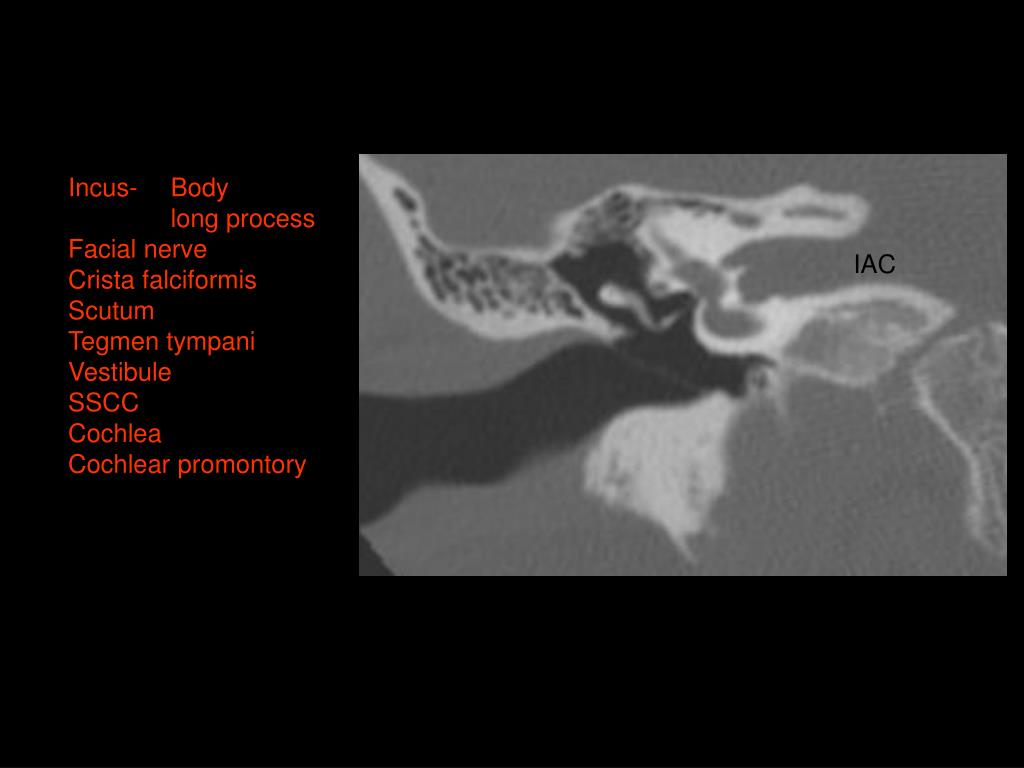

9. Incus- Body long process Facial nerve Crista falciformis Scutum Tegmen tympani Vestibule SSCC Cochlea Cochlear promontory IAC